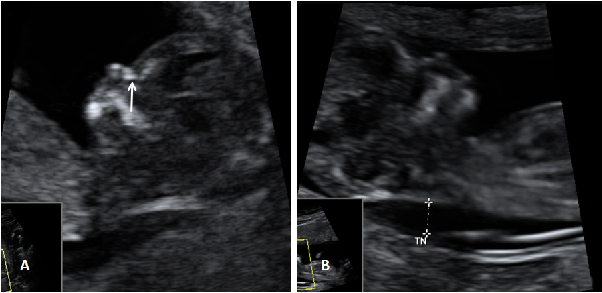

Con la ecografía de la semana 12 de embarazo se pueden detectar algunos signos (marcadores) característicos de los fetos con alguna anomalía cromosómica. Uno de ellos es el ángulo que forman el maxilar superior y el hueso frontal.

Qué mide el ángulo frontomaxilar del bebé

Se mide el ángulo que forman el maxilar superior y el hueso frontal. Los valores están tabulados por semana de embarazo. Cuándo este ángulo es mayor de lo normal, existe mayor riesgo de que ese feto tenga síndrome de Down. Es anormal en aproximadamente el 45% de los fetos con síndrome de Down.